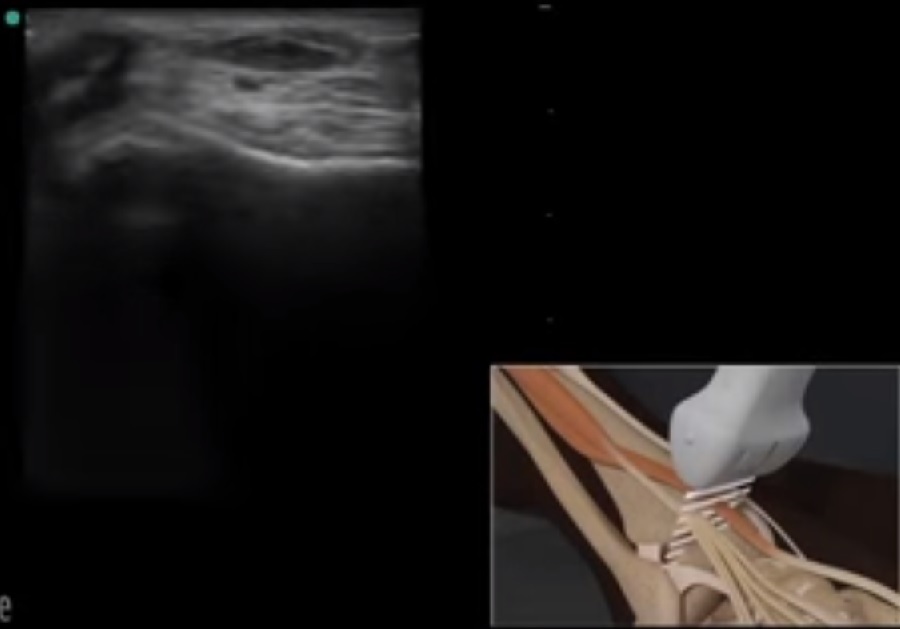

Imagen de la posición del transductor en el extensor largo del dedo gordo en el pie y el tobillo